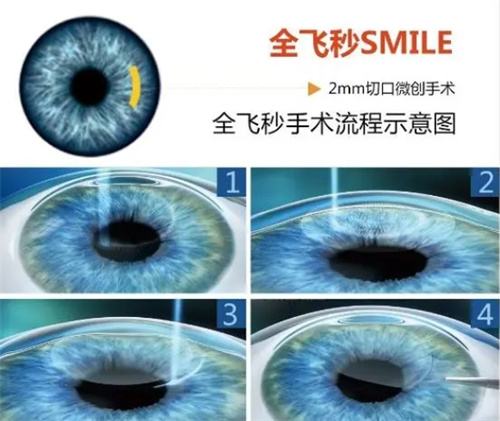

全飞秒激光手术:15800元/双眼